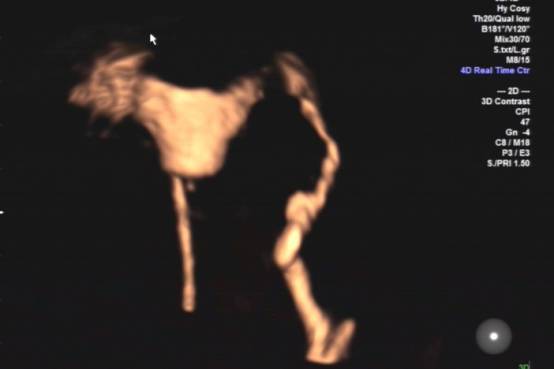

双输卵管不通

“操作中将造影剂经置入宫腔的导管注入子宫腔和输卵管腔,显示子宫腔和输卵管腔的形态、位置,发现宫腔和输卵管内病变、畸形以及评估输卵管通畅度。超声造影剂对人体无毒害,进入体内后迅速排出,对生殖系统无影响,超声造影技术操作简单、创伤轻微、安全、重复性好及检验输卵管通畅度的高准确性等优势,子宫输卵管超声造影也可使轻度粘连的输卵管得到疏通。”熟练开展该技术的医生陈谦谦介绍,若结果为输卵管通畅,下一月经周期即可实施助孕方案,可能使患者受孕时间提前,故对生殖时间窗影响小。经阴道超声造影探头的出现使患者无需憋尿、不受肥胖及肠道气体的干扰,从而显著提高了诊断的准确率。

右侧输卵管不通左侧输卵管通畅

双输卵管通畅